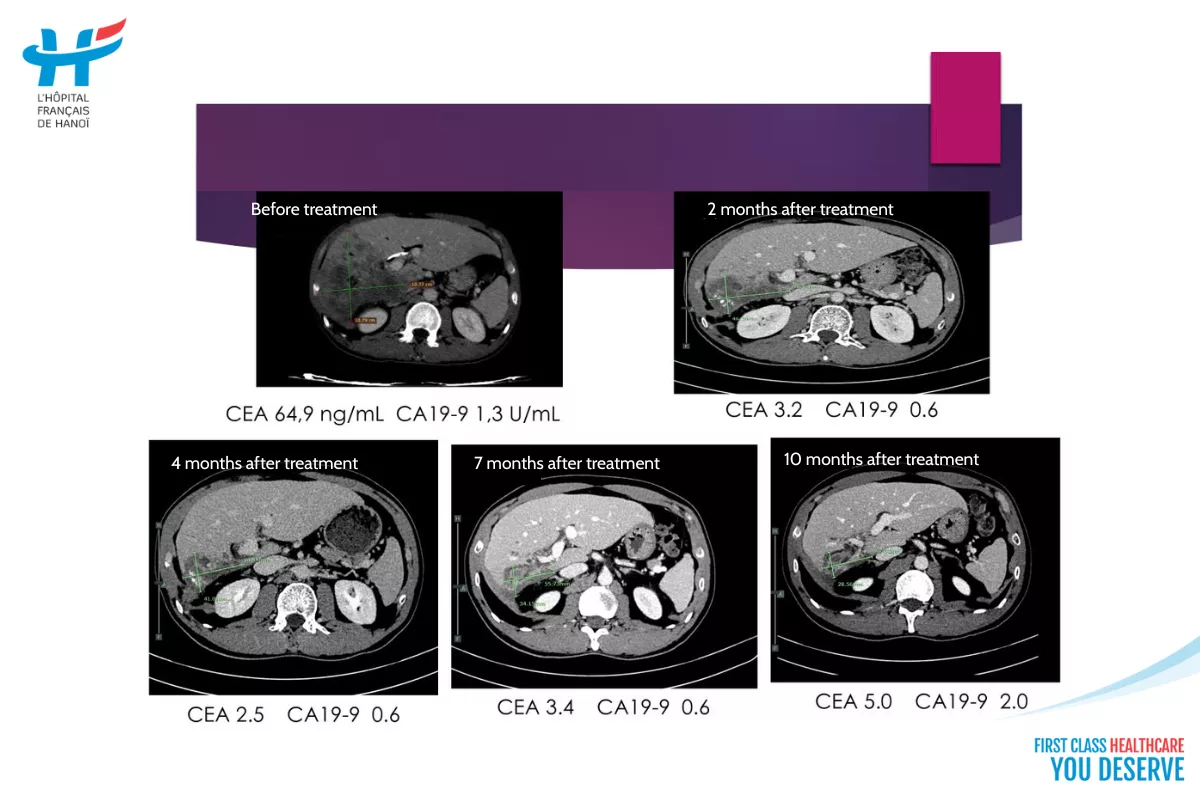

The presentation also provided examples of cases currently being monitored and treated by Dr. Lộc and his team. One such case involves a biliary cancer patient with metastasis to multiple organs. After 10 months of treatment with targeted therapy combined with chemotherapy, the tumor size reduced from 11x11cm to 5.7×2.8cm, and the patient is now under stable observation.